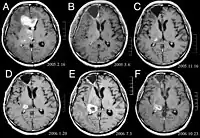

Primært centralnervesystem lymfom tegner sig for omkring 2 procent til 3 procent af alle hjernetumorer hos patienter med et normalt immunsystem. De forekommer hyppigere hos mænd over 55 år op til 60 år op. Næsten halvdelen af alle lymfomer forekommer hos patienter over 60 år og omkring en fjerdedel hos patienter over 70 år år op. Forekomsten ser ud til at stige med alderen, men årsagen er stadig uklar. Patienter med et svækket immunsystem har større risiko for at udvikle CNS-lymfom, så dem, der har fået foretaget en organtransplantation, har en medfødt immundefekt eller autoimmun sygdom eller er inficeret med human immundefektvirus. HIV-associerede hjernelymfomer er forbundet med Epstein-Barr-virus, især hos patienter med CD4-lymfocyttal under 500 celler pr kubikmillimeter i blodet. De fleste CNS-lymfomer er diffuse store B-celle lymfomer af typen.

Patienter lider af en række karakteristiske symptomer på en fokal eller multifokal massiv læsion. MR viser sædvanligvis tumorer med homogen kontrastforøgelse i den dybe periventrikulære hvide substans. Multifokalitet og inhomogen forbedring er typisk for patienter med et svækket immunsystem. Analyse af CNS-lymfom er ekstremt vigtig i differentialdiagnosen af hjerneneoplasi. Det skal bemærkes, at administration af kortikosteroider kan føre til fuldstændig forsvinden af forstærkningen, hvilket gør diagnosen af læsionerne vanskelig. Hvis CNS-lymfom skal overvejes i differentialdiagnosen, bør kortikosteroider derfor undgås, medmindre masseeffekten forårsager et alvorligt og umiddelbart problem hos patienten.

Biopsi af den formodede læsion er afgørende. I modsætning til systemisk storcellet B-celle lymfom, hvor både kemoterapi og strålebehandling er effektive, og behandling af lokaliserede læsioner er helbredende, reagerer lymfom i centralnervesystemet typisk på den indledende behandling, men kommer derefter igen. Som med systemisk lymfom er operationens rolle primært begrænset til at få passende vævsprøver til diagnosticering.

Tidligere blev strålebehandling givet til hele hjernen (panencefalisk). Medianoverlevelsen er omkring 12 selv med lokaliserede læsioner måneder. Gentagelse påvirker normalt stedet for den tidligere skade såvel som andre regioner. Reaktioner på kemoterapi er mere lovende. Kliniske forsøg, hvor højdosis methotrexat alene blev brugt som den første behandling, og strålebehandling blev forsinket indtil tidspunktet for tilbagefald eller progression viste bedre samlet overlevelse end strålebehandling alene. Endnu mere effektiv var kombinationen af methotrexat, vincristin, procarbazin, intrathecal methotrexat, cytarabin og panencefalisk strålebehandling og cytarabin, eller brugen af intraarteriel kemoterapi med intraarteriel methotrexat, intravenøst injiceret cyclophosphamid og etoposid efter modifikation af blodet. hjernebarriere med mannitol. Medianoverlevelsen i methotrexatbehandling var 24 indtil 40 måneder meget højere end med strålebehandling alene (interval 24 så længe 40 måneder). I nogle tilfælde bruges strålebehandling kun ved tilbagefald, når der er en indledende regression med kemoterapi. Tilfælde af lang overlevelse er også blevet rapporteret uden strålebehandling.